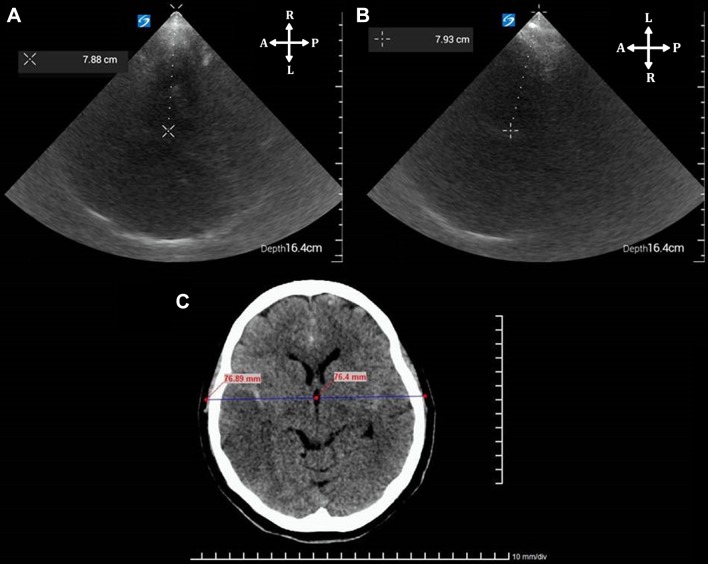

Midline shift

The midline shift (MLS) is evaluated in the diencephalic plane. A first measurement (“A”) is taken from the start of the ultrasound beam to the center of the third ventricle. A second (“B”) is taken in the same way by insonating from the contralateral side. MLS is calculated as (A − B)/2 (Fig. 16). A good correlation with CT has been demonstrated in several studies. An MLS > 2.5 mm on TCCS is considered significant and its detection is helpful in deciding the optimal time to perform a new TC [15, 27, 28].

Fig. 16.

Technique for measurement of MLS. A and B distances are obtained from the start of the ultrasound beam to the center of the third ventricle, bilaterally. a A distance is 78.8 mm (right transtemporal view). b B distance is 79.3 mm (left transtemporal view). MLS = (A − B)/2. The MLS is negligible, measuring 0.25 mm leftward, correlating with cranial CT in c

In cases of decompressive craniectomies, cephalohematomas, skull fractures or evident cranial asymmetries, this method of measuring the MLS is inaccurate. Particularly for decompressive craniotomies, a direct method of measuring the MLS, with a good correlation with the CT, consists of insonating over the skull defect and measuring the deviation of the septum pellucidum in comparison with the midline given by the cerebral falci [29].